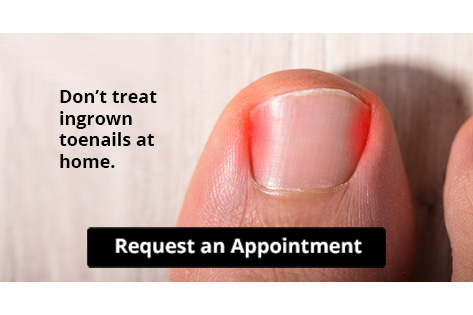

Let the Expert Treat Your Ingrown Toenails

Ingrown toenails are a common and sometimes painful condition in which the edges of a nail grow into the surrounding skin instead of over it. This leads to tenderness, swelling, redness, and pain. In some cases, the area can even become infected. One of the main causes of ingrown toenails is trimming the toenails incorrectly. When you trim your toenails, you should use a nail clipper rather than scissors. Trim the nails straight across and not too short. Though it may be tempting for aesthetic reasons, do not round the edges of your toenails with clippers, scissors, or a nail file. Rounded edges make ingrown nails more likely. To complement your properly trimmed toenails, wear comfortable shoes with a wide toe box. Tight, narrow, or pointy-toed shoes can squish the toes together and push the nails into the surrounding skin. To learn more about how to prevent ingrown toenails, please speak with a podiatrist.

Ingrown toenails can become painful if they are not treated properly. For more information about ingrown toenails, contact the foot specialists of Spartan Podiatry. Our doctors can provide the care you need to keep you pain-free and on your feet.

Ingrown Toenails

Ingrown toenails occur when a toenail grows sideways into the bed of the nail, causing pain, swelling, and possibly infection.

Causes

- Bacterial infections

- Improper nail cutting such as cutting it too short or not straight across

- Trauma to the toe, such as stubbing, which causes the nail to grow back irregularly

- Ill-fitting shoes that bunch the toes too close together

- Genetic predisposition

Prevention

Because ingrown toenails are not something found outside of shoe-wearing cultures, going barefoot as often as possible will decrease the likeliness of developing ingrown toenails. Wearing proper fitting shoes and using proper cutting techniques will also help decrease your risk of developing ingrown toenails.

Treatment

Ingrown toenails are a very treatable foot condition. In minor cases, soaking the affected area in salt or antibacterial soaps will not only help with the ingrown nail itself, but also help prevent any infections from occurring. In more severe cases, surgery is an option. In either case, speaking to your podiatrist about this condition will help you get a better understanding of specific treatment options that are right for you.